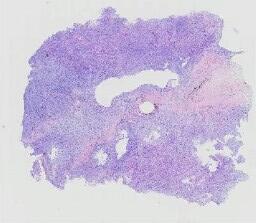

临床资料: 患者女性,71岁,发现甲状腺结节10+天。患者无意间发现甲状腺结节,结节无痛,初期无呼吸困难,表面皮肤无红肿,无食欲亢进、消瘦、手抖、饮水呛咳等不适,无怕热多汗及性情改变,无发热、寒战、心慌不适。患者至武胜县中医院就诊,甲状腺彩超提示甲状腺左叶4c类结节,大小约22*27*33mm,左颈IV见淋巴结增大,结构显示不清。

大体所见: 灰白结节一个,大小4cm×3cm×3cm,表面附着少许甲状腺,切面灰白、实性、质中偏韧,见坏死。